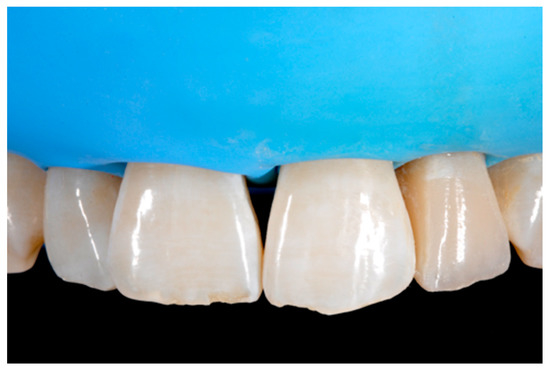

A wise balance of these opaque and translucent shades represents the key factor in obtaining reliable esthetic outcomes and great attention should be paid for their correct positioning [10,27]. Nevertheless, it happens that, during the restorative procedures, some inaccuracies could be made resulting in having opaque shades in place of translucent ones. This is generally realized too late, after finishing and polishing procedures thus compromising the final esthetic result [25]. In Figure 58 in fact the esthetic outcome of the left central incisor could have been improved if the opaque incisal margin had been made thicker and festooned. Conversely, we can notice from Figure 59 excessive thickness in the opaque incisal margin that, if not reduced, could provide an unpleasant final esthetic result.

Figure 58.

A more accurate management of the frame could have improved the thin and not festooned incisal opaque margin on left central incisor.

Figure 59.

Completing the restorations without previously reducing the incisal frame could provide an unpleasant final esthetic outcome.